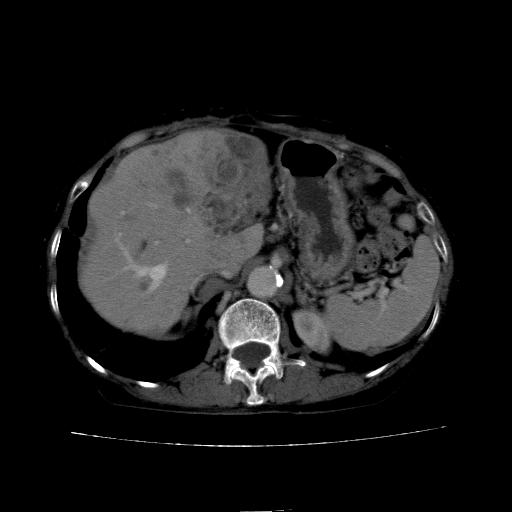

动脉期

看片子胆管里结石,肝上显示的占位会不会是胆管癌?大家帮忙看看,图像不太好,手头的处理文件没有,大致转换了一下,有原始图像数据

1)考虑肝左叶胆管细胞癌并肝内转移。2)肝左叶肝内胆管结石。